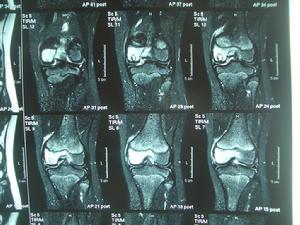

骨膜炎是一種多發性骨科疾病,其發病部位主要在膝關節。是骨膜受到刺激產生炎症,造成分泌液失調形成積液的一種關節病變。膝關節是全身關節中骨膜最多的關節,故骨膜炎以膝為多見。膝關節滑膜炎主要是因膝關節扭傷和多種關節內損傷,而造成的一組綜合症。容易造成患者暫時或長期部分喪失勞動力,無論對患者和對社會的危害都較大,骨膜炎較為嚴重。

骨膜炎局部疼痛、局部充血水腫、活動障礙。血源性骨髓炎早期有局部劇烈疼痛和跳痛,肌肉有保護性痙攣,肢體不敢活動。患部腫脹及壓痛明顯。如病灶接近關節,則關節亦可腫脹,但壓痛不顯著。當膿腫穿破骨質、骨膜至皮下時,即有波動,穿破皮膚後,形成竇道,經久不愈。

2.急性化膿性關節炎,腫脹、壓痛在關節間隙而不在骨端,關節動度幾乎完全消失,有疑問時,關節腔穿刺抽液檢查可明確診斷。

2.局部症狀 血源性骨髓炎早期有局部劇烈疼痛和跳痛,肌肉有保護性痙攣,肢體不敢活動。患部腫脹及壓痛明顯。如病灶接近關節,則關節亦可腫脹,但壓痛不顯著。當膿腫穿破骨質、骨膜至皮下時,即有波動,穿破皮膚後,形成竇道,經久不愈。